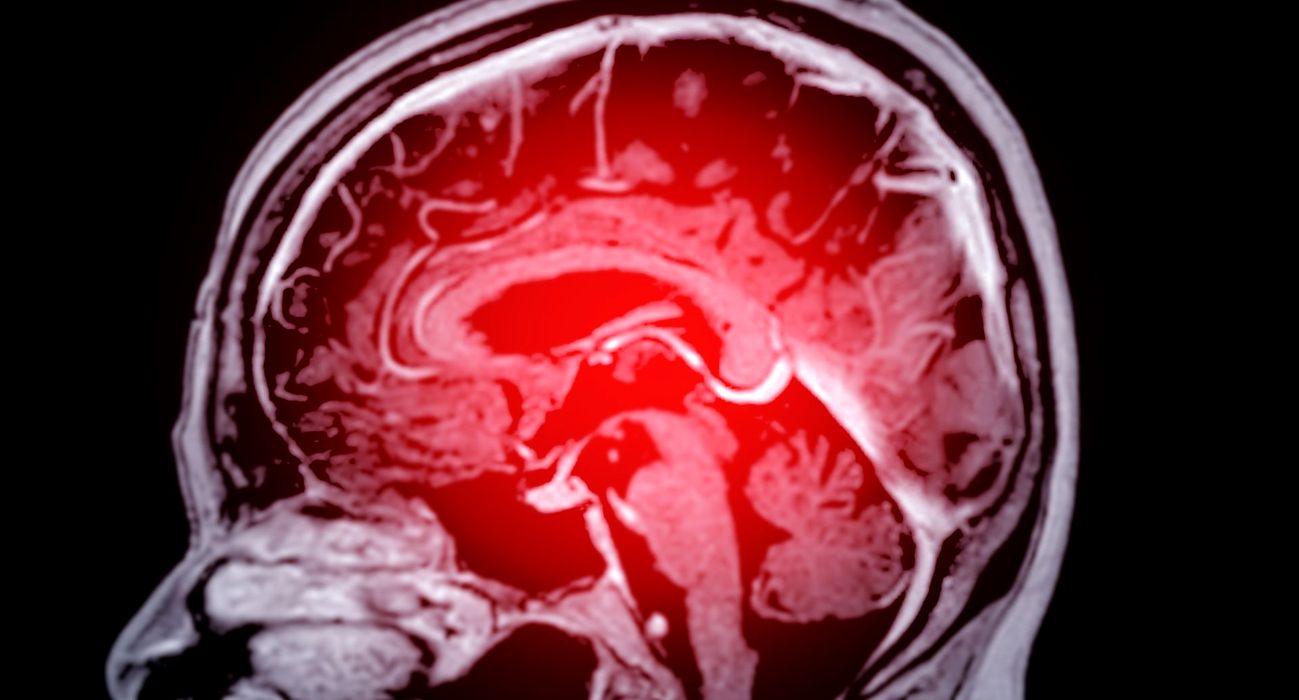

Educația, ocupația și averea influențează riscul de deteriorare cognitivă

Factorii socioeconomici precum educația, ocupația și bunăstarea influențează riscul de deteriorare cognitivă sau demență la vârsta înaintată, dar și posibilitatea ca o persoană să se recupereze, arată un nou studiu condus de cercetătorii de la […]